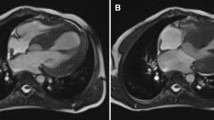

Further analysis of global myocardial function was performed with Speckle tracking echocardiography (GLS). Cardiac magnetic resonance imaging (CMR) imaging studies were performed on two patients (Patients A and C) to assess cardiac anatomy.

CMR was performed on two children and had evidence of decreased left ventricular function. Strain parameters of the left ventricle, including GLS, were calculated in three available patients. GLS of the left ventricle was abnormal in three children (Fig. 2).